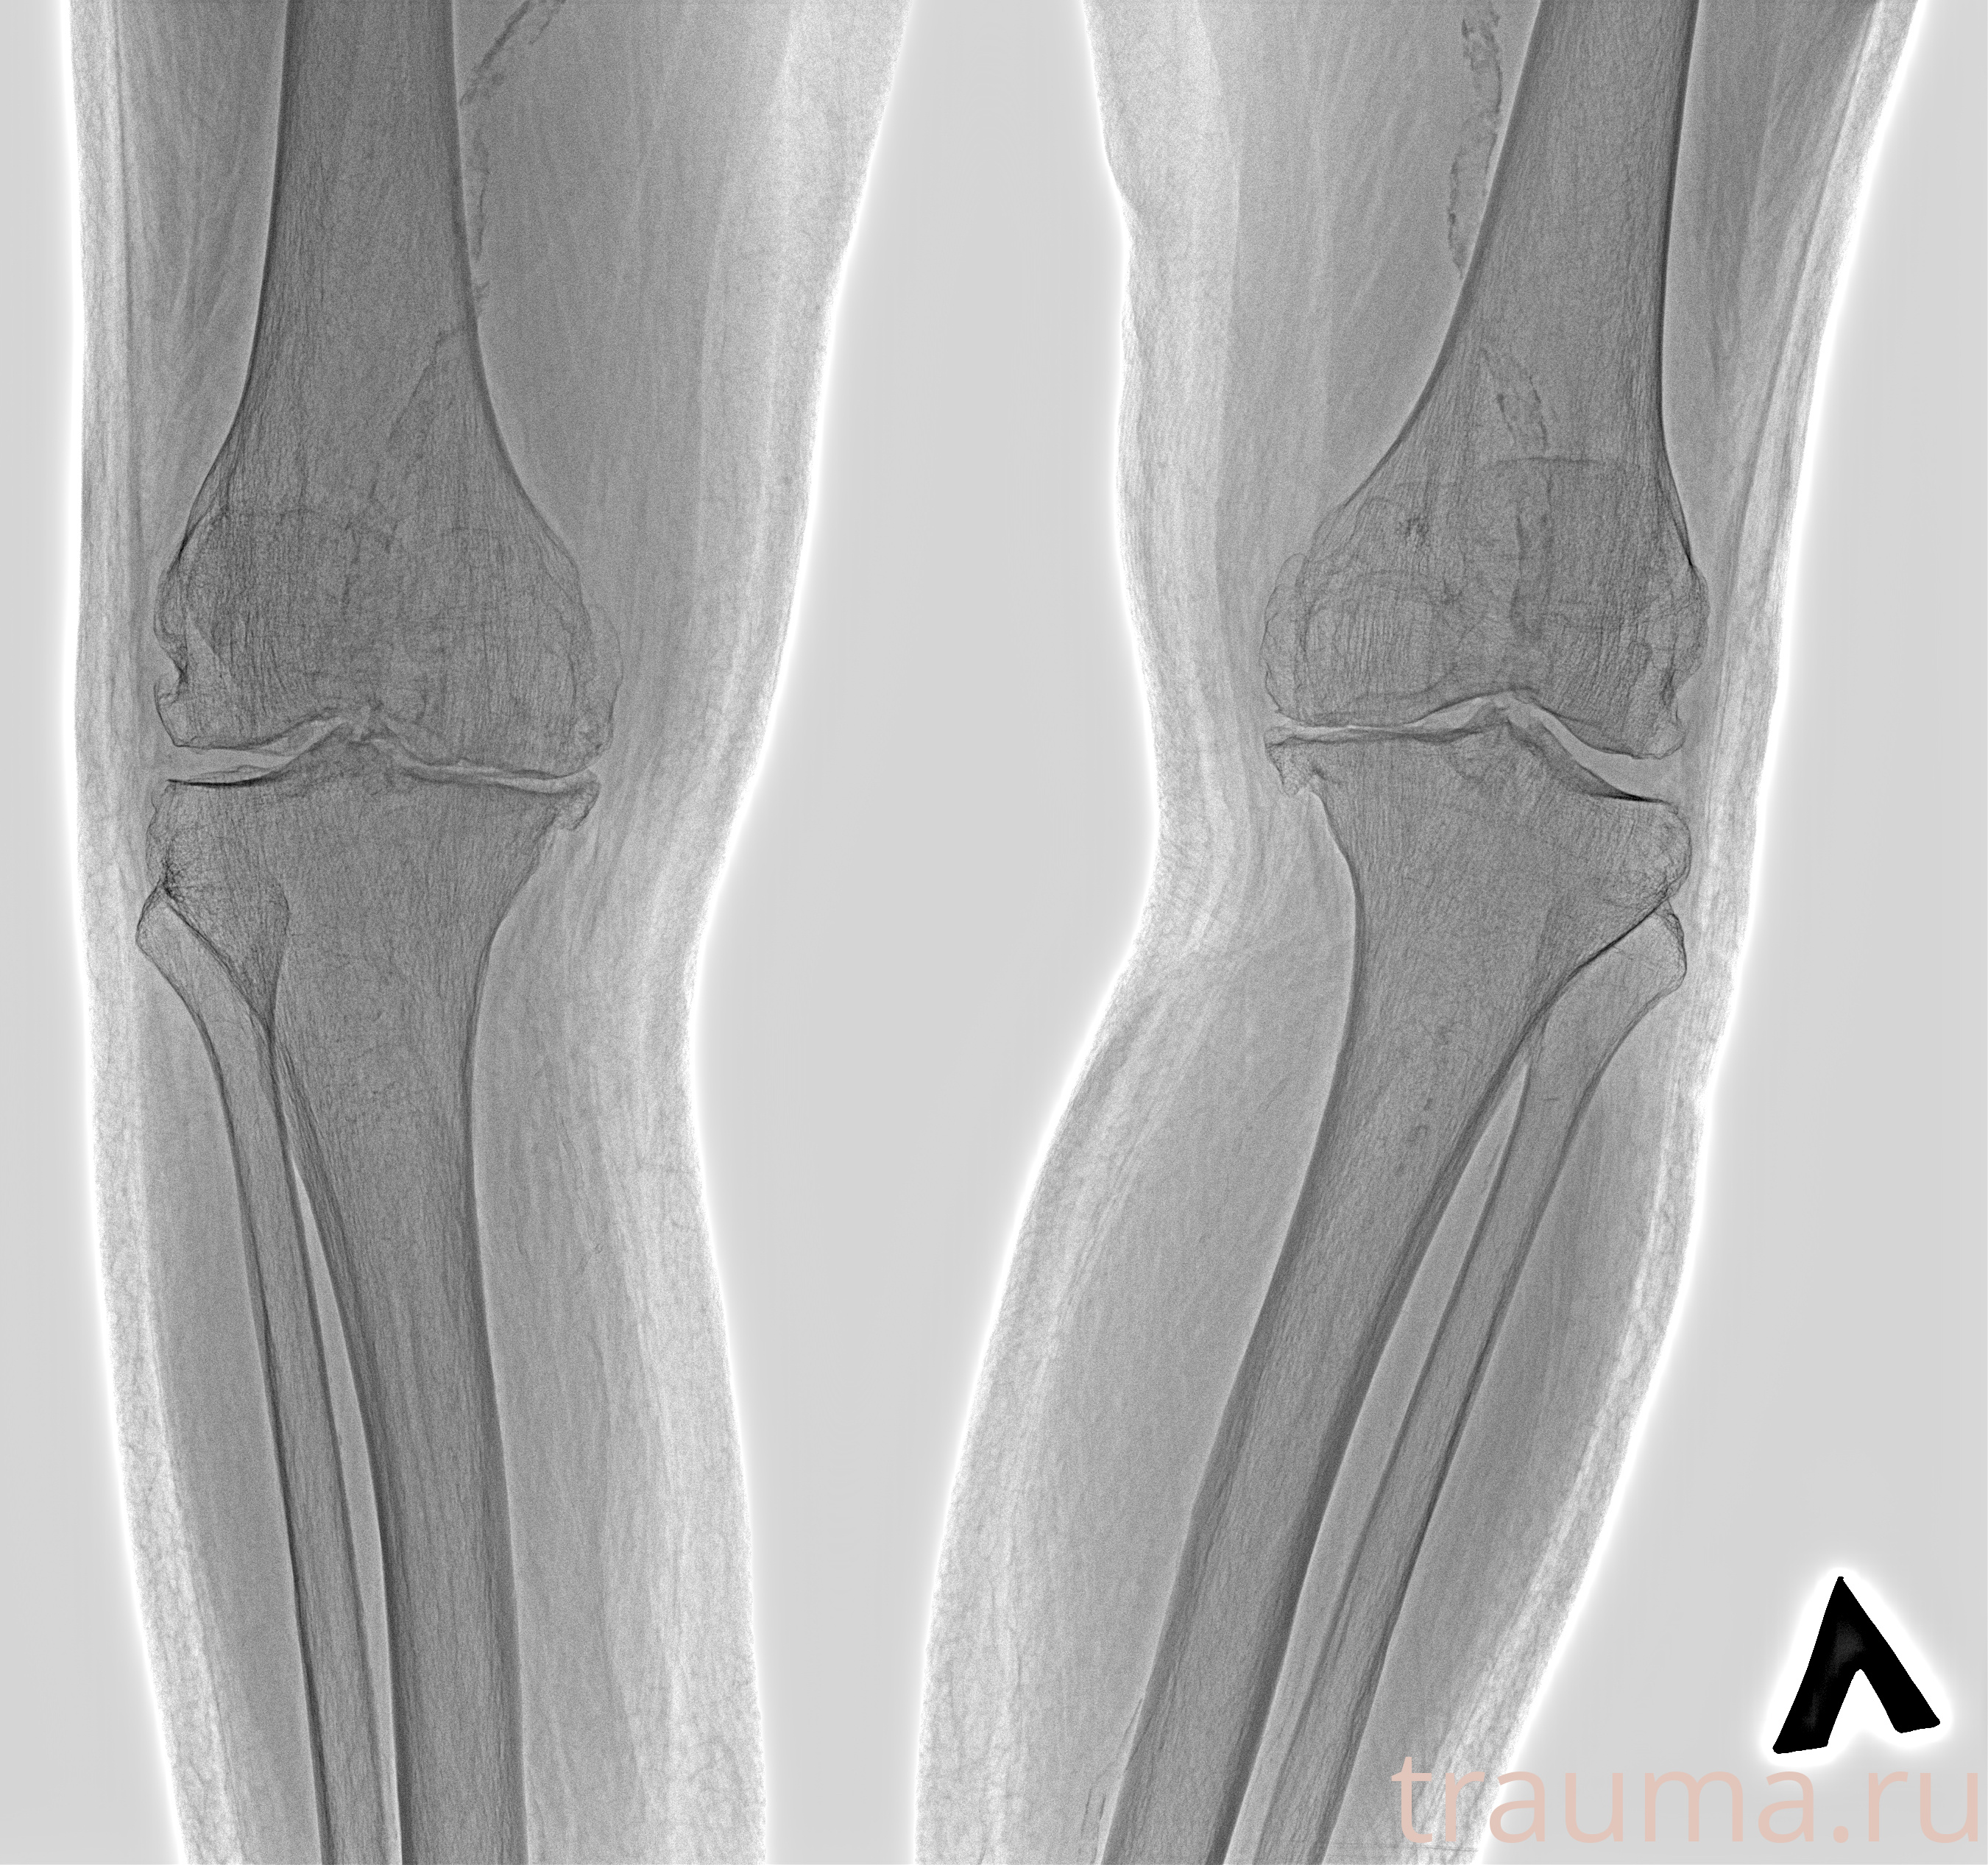

Рентген на дому: по вашему адресу приезжает врач-рентгенолог, травматолог-ортопед с мобильным рентгеновским аппаратом, проводит диагностику травмы или заболевания, делает необходимые рентгенограммы, дает рекомендации по дальнейшему лечению. Получить качественные снимки в домашних условиях возможно благодаря уникальной методике, разработанной МосРентген Центром для института  Склифосовского